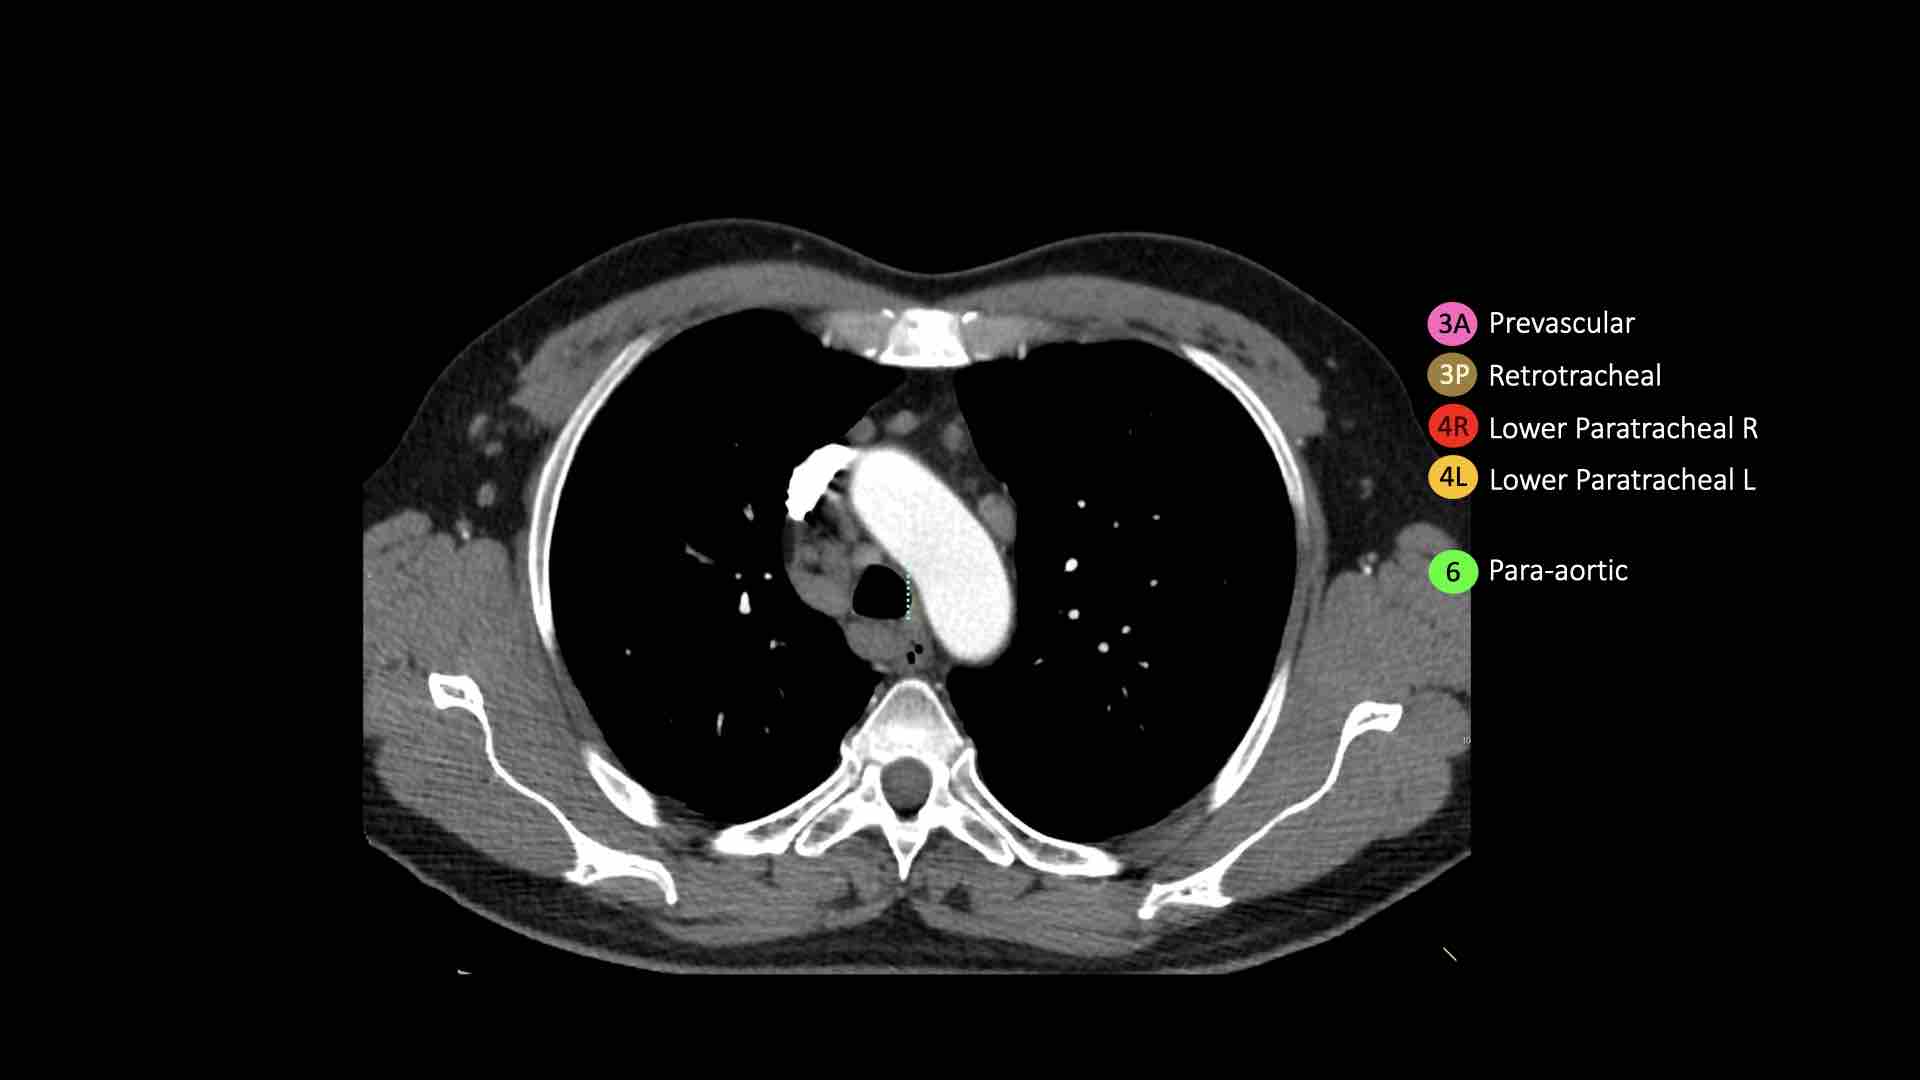

3A.Trước mạch máu

Các hạch này không tiếp giáp với khí quản như các hạch ở nhóm 2, mà nằm ở phía trước các mạch máu.

3P.Trước cột sống

Các hạch không tiếp giáp với khí quản như các hạch ở nhóm 2, mà nằm sau thực quản, tức là ở vị trí trước cột sống.

4R.Cạnh khí quản dưới

Từ điểm giao nhau giữa bờ dưới tĩnh mạch vô danh (tĩnh mạch tay đầu trái) với khí quản đến bờ dưới tĩnh mạch đơn.

Hạch nhóm 4R trải dài từ bờ bên phải đến bờ bên trái của khí quản.

4L.Cạnh khí quản dưới

Từ bờ trên của quai động mạch chủ đến bờ trên của động mạch phổi trái.

6. Cạnh động mạch chủ

Đây là các hạch của động mạch chủ lên hoặc hạch cơ hoành, nằm ở phía trước và bên của động mạch chủ lên và quai động mạch chủ.

Bên trái là hạch 3A nằm trong khoang trước mạch máu.

Lưu ý cũng có các hạch cạnh khí quản dưới bên phải, tức là hạch nhóm 4R.

Bên trái là hạch cạnh khí quản 4R.

Ngoài ra còn có một hạch động mạch chủ nằm bên ngoài quai động mạch chủ, tức là hạch nhóm 6.

Bên trái là hình ảnh ngay trên mức thân động mạch phổi, cho thấy các hạch cạnh khí quản dưới bên trái và bên phải.

Ngoài ra còn có các hạch nhóm 3 và nhóm 5.

Bên trái là hình ảnh ở mức phần dưới khí quản, ngay trên carina.

Bên trái khí quản là các hạch 4L.

Lưu ý rằng các hạch 4L này nằm giữa thân động mạch phổi và động mạch chủ, nhưng không nằm trong cửa sổ phế động mạch, vì chúng nằm ở phía trong dây chằng động mạch.

Hạch nằm bên ngoài thân động mạch phổi là hạch nhóm 5.